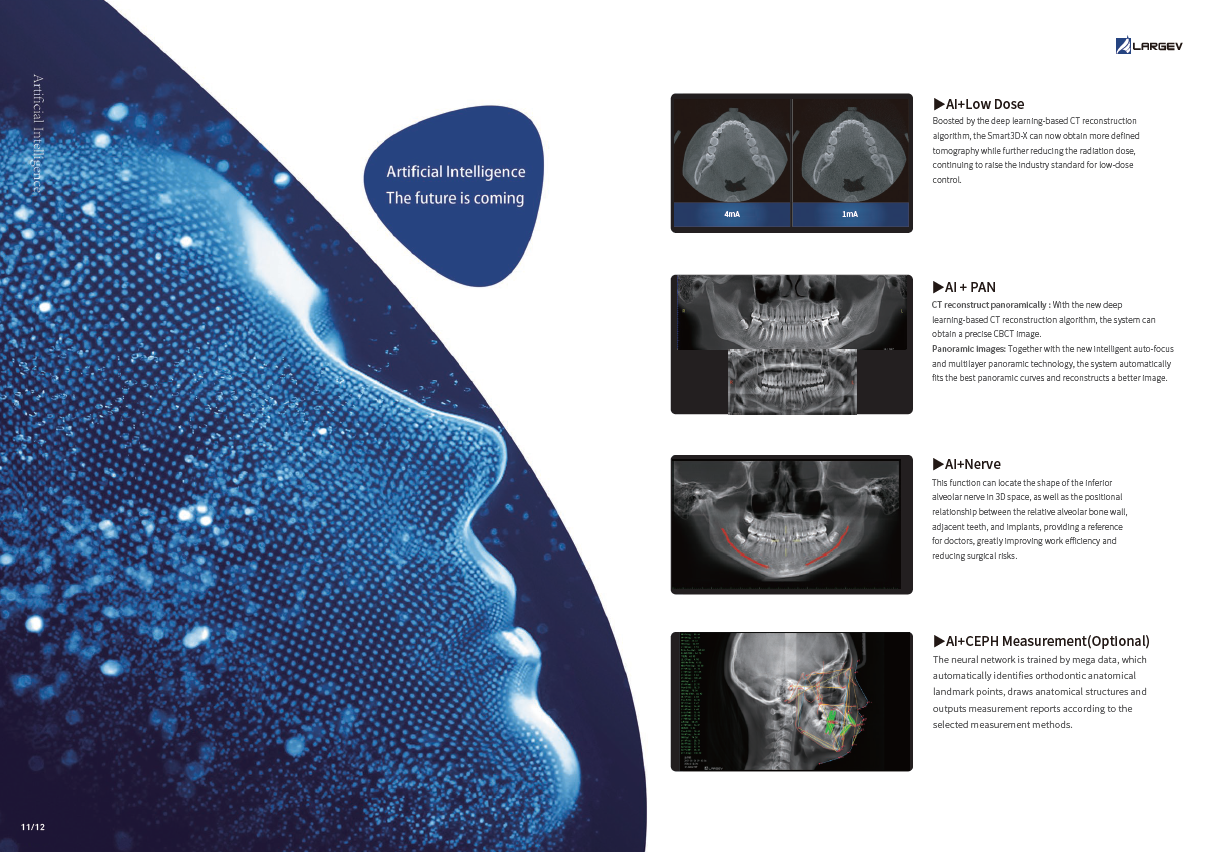

AI + Low-Dose Dental CBCT Technology

- The integrated AI image processor enhances CT quality while reducing radiation exposure.

Consequently, each 3D scan provides superior clarity at a lower dose, ensuring patient safety.

Next, Nerve Detection with Dental CBCT (AI+Nerve)

The system automatically identifies and labels the neural tube within the CT image.

This function simplifies diagnosis and supports more precise surgical planning.

Furthermore, AI+PAN Dental CBCT Imaging enhances precision.

- The system rebuilds panoramic views directly from CBCT data using AI.

- Panoramic auto-focus and multi-layer technology select the best curve automatically.

- Therefore, the final image is cleaner and easier to read.

Finally, CEPH Measurement (Optional) in Dental CBCT (AI+CEPH)

The AI model analyzes large data sets to detect orthodontic landmarks and generate accurate cephalometric measurements and reports.

Therefore, orthodontists can assess and plan treatments with confidence.